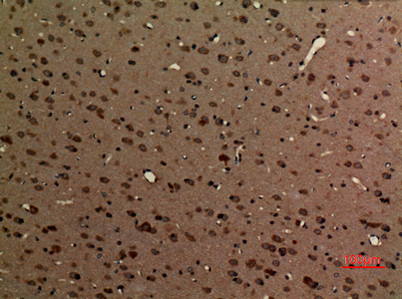

Product name: Myosin VI rabbit pAb

Dilutions: Western Blot: 1/500 - 1/2000. IHC-p: 1:100-300 ELISA: 1/5000. Not yet tested in other applications.

Immunogen: Synthesized peptide derived from Myosin VI . at AA range: 40-120